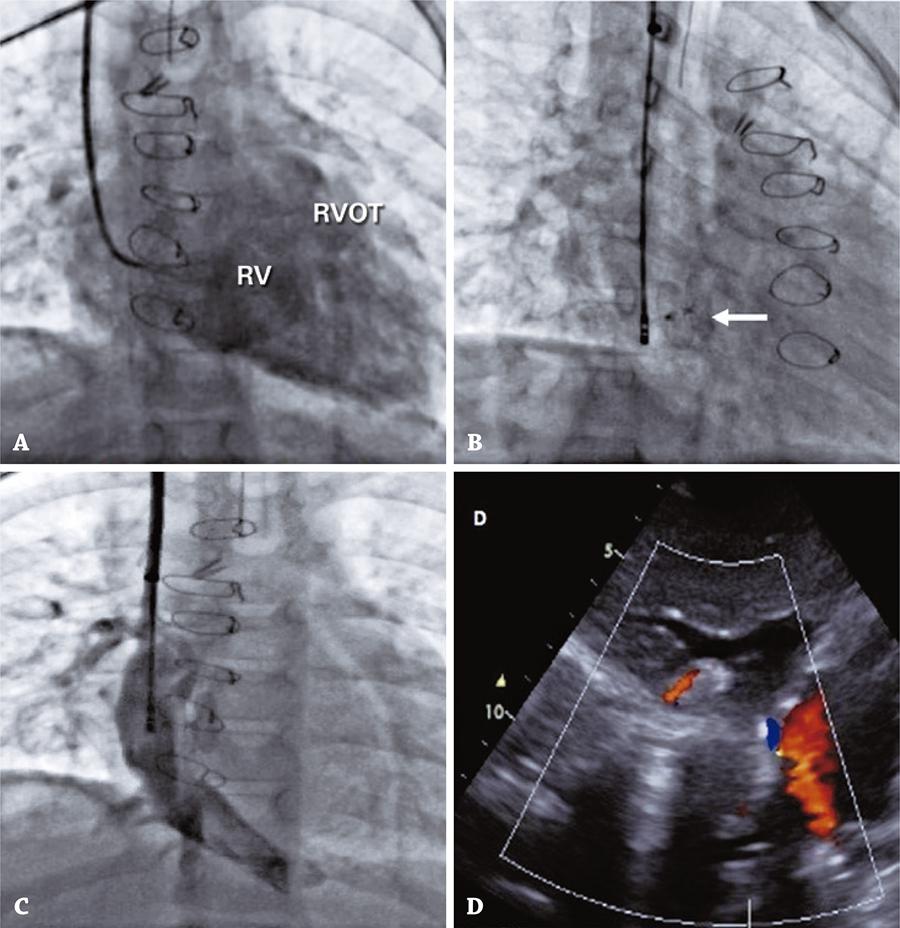

Ten procedures were conducted in ten patients; in that, four Glenn (Group I) and six Fontan (Group II). The mean age in Groups I and II was 86 months and 106 months, and the mean time since surgery was 24 months and 25 months, respectively. Six patients had obstructive lesions and four had venovenous shunts, systemic-pulmonary anastomosis or a fenestrated cavopulmonary tube. In cases with obstructive lesions, there was no residual gradient; after dilation, there was a significant increase or normalization of vessel diameter. In patients with shunts, there was complete occlusion after deployment of the device. In all cases hemodynamic parameters normalized, clinical status improved and there were no complications.